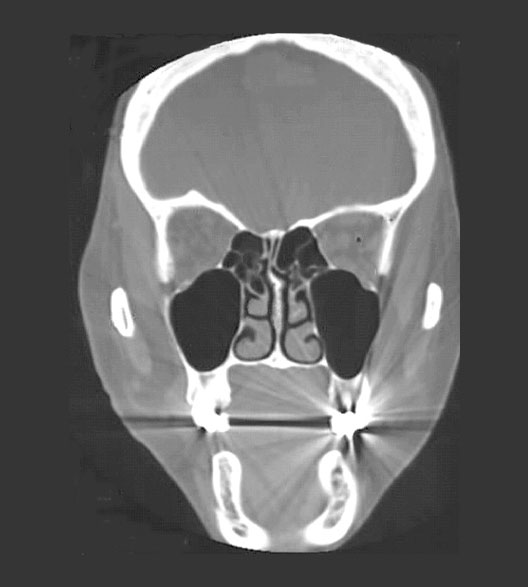

Head CT Coronal

Roll mouse over image to display labels.

1. Ethmoid air sinus

2. Middle concha

3. Maxillary air sinus

4. Inferior concha

5. Brain

6. Eyeball

7. Temporalis muscle

8. Nasal septum

9. Mandible

10. Hard palate

11. Metal filling in tooth